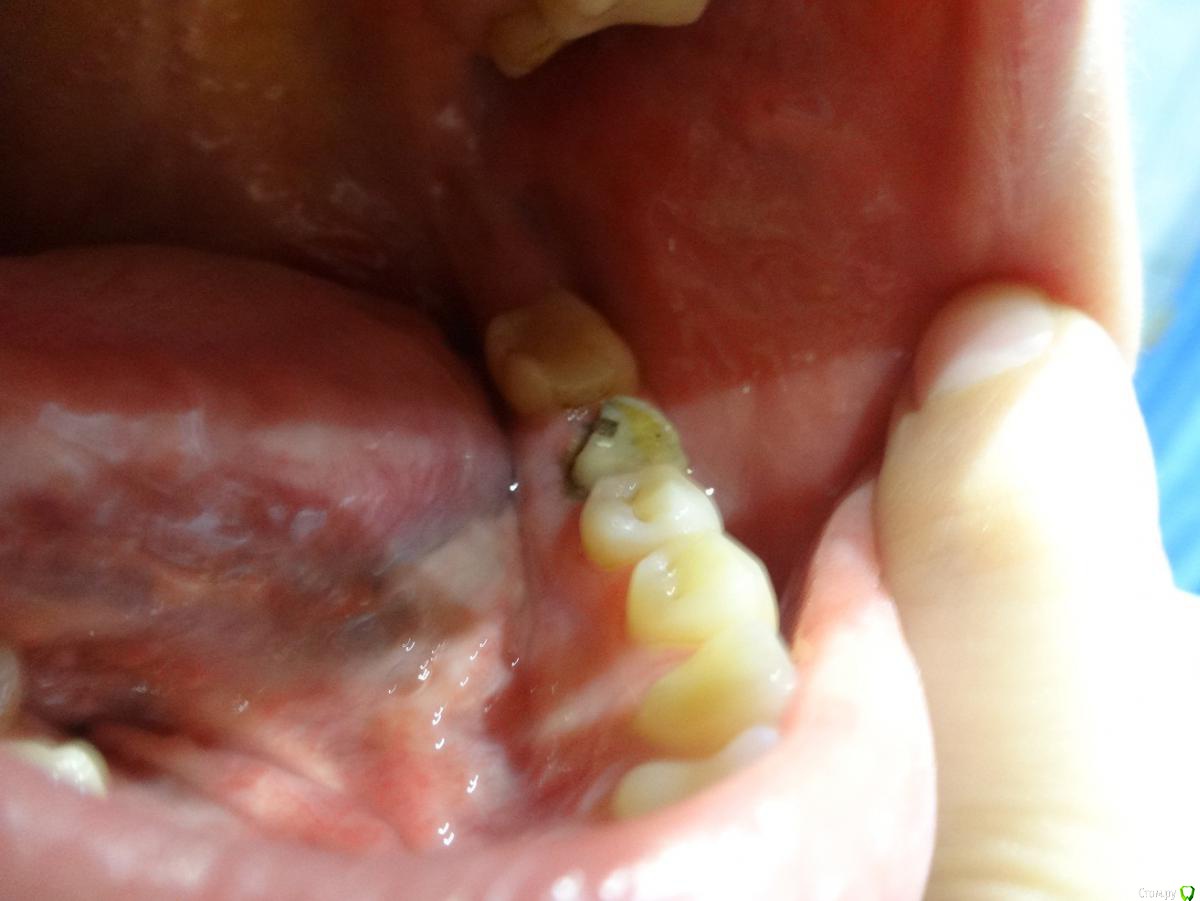

lepestochek Опубликовано 5 ноября, 2015 Поделиться Опубликовано 5 ноября, 2015 (изменено) Здравствуйте! Хотелось бы услышать профессиональную оценку по поводу жевательного зуба 36. Более 10 лет на нём стояла коронка. На снимке врач увидел воспаление у корня и предложил протезирование коронкой из диоксида циркония и, вероятно, вкладка( точно скажет на следующем приёме), предварительно пролечив каналы. После чего воспаление должно со временем исчезнуть. Коронку сняли( фото). На внутренней стороне нет стенки, поэтому хотелось бы знать надёжно ли будет предложенное лечение. А если и возможно, то нельзя ли металлокерамической коронкой накрыть? 15 зуб подготовили под культевую вкладку из кобальт хрома и коронки из диоксида циркония, так как металлокерамика сказали не будет держаться. И это немалые деньги. Ещё раз прошу, подскажите, стоит ли 36 зуб таких затрат? Спасибо. Изменено 5 ноября, 2015 пользователем lepestochek Ссылка на комментарий

4ebstom Опубликовано 6 ноября, 2015 Поделиться Опубликовано 6 ноября, 2015 36-печально,что нет язычной стенки зуба.Если восстанавливать-я бы кхс вкладка+цельная цирк.коронка. Ссылка на комментарий

Larnary Опубликовано 6 ноября, 2015 Поделиться Опубликовано 6 ноября, 2015 Цельноциркон будет стачивать антагонисты. Я бы в данной ситуации выделил 2 главных момента:-на сколько глубоко под десну разрушена язычная стенка. По таким фото можно только гадать.-успешность эндодонтического лечения. Ссылка на комментарий